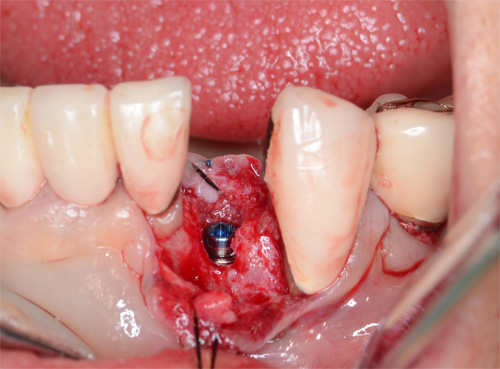

この日の手術は下の前歯1本を埋入する手術でした。

術中写真です。最初の細いドリルでサージカルガイドを使って骨に穴を開けているところです。

使用したのはストローマン社の直径2.9mm長さ10mmのインプラント

コンピューターシュミレーションシステムによりこれを選択しました。

埋入しました、骨幅狭いです。

縫合してオペ終了です